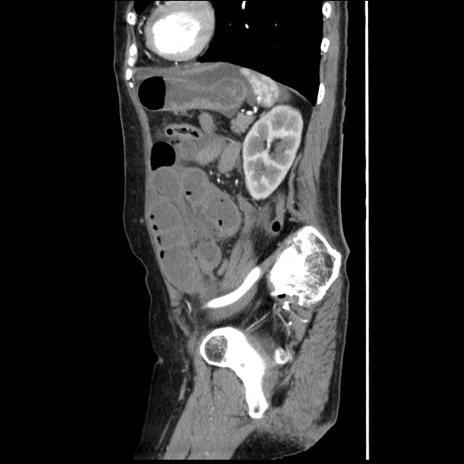

冠状断像

【症例】80歳代女性

【主訴】腹痛

【現病歴】8時間前から腹痛あり来院。

【既往歴】糖尿病、脂質異常症、子宮体癌にて子宮全摘術

【身体所見】意識清明・会話良好だが腹痛で苦悶様、全腹部にわたって反跳痛と圧痛あり

【データ】WBC 13600、CRP 0.14、LDH 224、CK 90